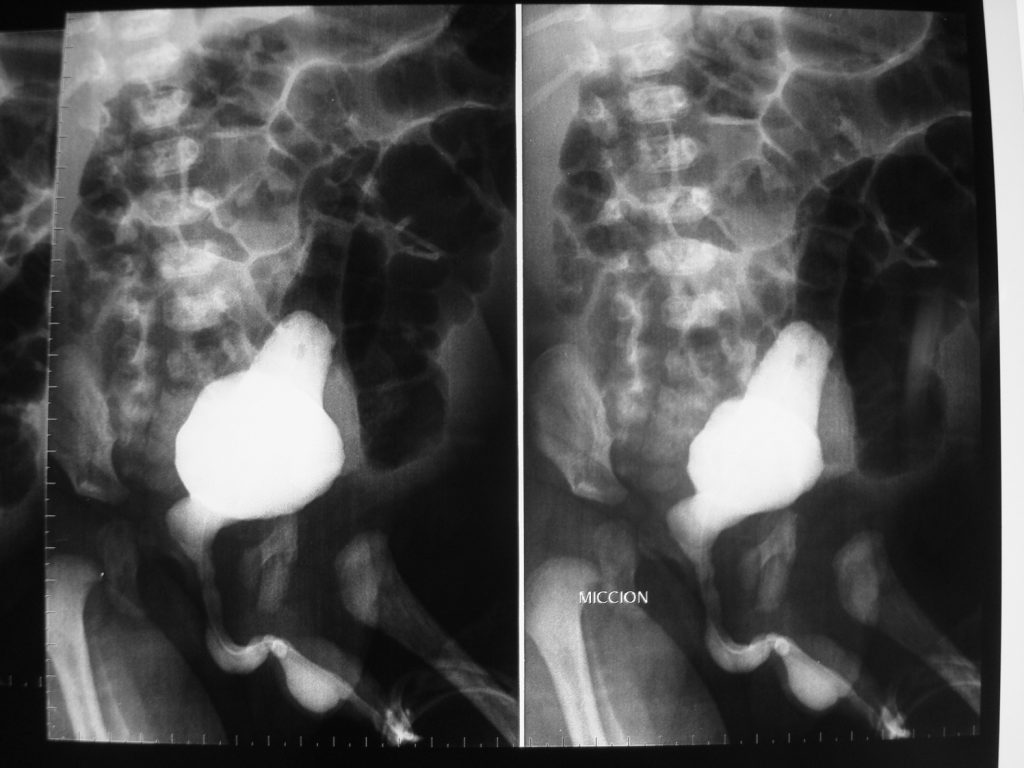

Uretrocistografía miccional: Provee información definitiva del diagnóstico con la imagen de dilatación de uretra posterior. Además, evidencia la presencia de RVU (40- 60% de los casos). Cistoscopia: Establece el diagnóstico definitivo ya que se observan directamente las VUP, además de poder realizar el tratamiento en el mismo acto quirúrgico. Se utiliza también para determinar el estado de la vejiga y de los meatos ureterales.

Manifestaciones genito urinarias: La displasia renal es la alteración más frecuente y generalmente es asimétrica. El compromiso renal es el principal factor pronóstico en estos pacientes. Se observa algún tipo de compromiso ureteral en todos los casos, especialmente hacia distal, secundario a hipoplasia de células de musculo liso, lo que se traduce en uréteres aperistálticos, dilatados y tortuosos. Existe asociación con RVU en un 75-85% de los casos. Se observa megavejiga con pseudodivertículo o persistencia del uraco, de paredes engrosadas a expensas de tejido conectivo, con un trígono grande, asimétrico y orificios ureterales en posición lateral. La compliance vesical es adecuada, la contractibilidad se ve comprometida en la mitad de los casos, lo que se ve reflejado en residuos postmiccionales elevados (figura 7). La uretra posterior se encuentra dilatada lo que podría explicarse por posible atresia, estenosis o válvulas hacia distal, lo que determina una próstata hipoplásica. La criptorquidea es uno de los pilares diagnósticos del síndrome, lo más común es que se encuentren intraabdominales, a nivel de los vasos iliacos. La fertilidad esta potencialmente disminuida, pese a que el estudio histológico es normal, por alteraciones en la maduración de las células germinales y por factores extratesticulares como disyunción epididimaria, pero eso no necesariamente implica que la paternidad este afectada.